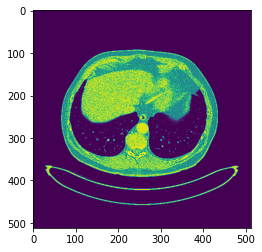

plt.imshow(X_train1[40].reshape(512, 512))

plt.imshow(y_train1[40].reshape(512, 512))

plt.imshow(X_train3[35].reshape(512, 512), cmap='gray')

plt.imshow(y_train3[35].reshape(512, 512), cmap='gray')